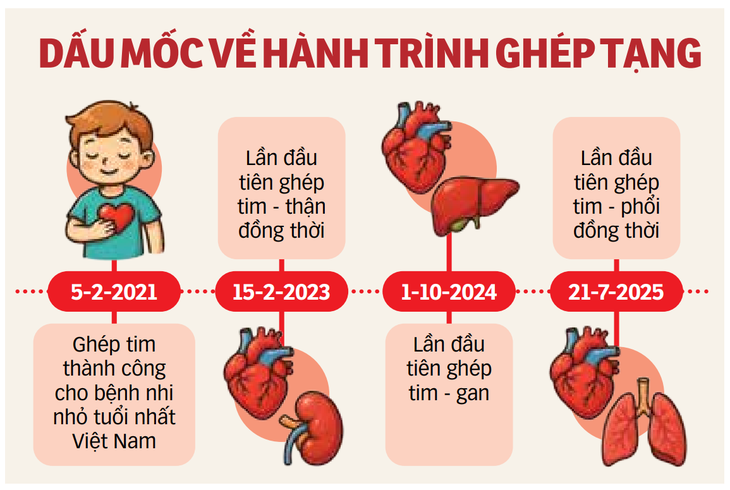

ក្រាហ្វិក៖ T.DAT

ចំណុចសំខាន់នៃដំណើរផ្លាស់ប្តូរសរីរាង្គ

មិនត្រឹមតែធ្វើអព្ភូតហេតុជាមួយការវះកាត់ប្តូរបេះដូង-សួតប៉ុណ្ណោះទេ មន្ទីរពេទ្យវៀតឌឹកបានឈានដល់ដំណាក់កាលជោគជ័យនៃការវះកាត់ប្តូរបេះដូងលើកទី១០០។

លោកវេជ្ជបណ្ឌិត Hung បានចែករំលែកថា ការប្តូរបេះដូង ដែលធ្លាប់ត្រូវបានចាត់ទុកថាជាបច្ចេកទេសដែលមានតែនៅក្នុងប្រទេសដែលមានប្រព័ន្ធវេជ្ជសាស្រ្ដជឿនលឿន ឥឡូវនេះបានក្លាយជាទម្លាប់នៅមន្ទីរពេទ្យមិត្តភាព Viet Duc។ ចាប់តាំងពីការប្តូរបេះដូងលើកដំបូង វេជ្ជបណ្ឌិតបានឆ្លងកាត់ការធ្វើដំណើររយៈពេល 13 ឆ្នាំ ដើម្បីឈានដល់ដំណាក់កាលនៃការប្តូរបេះដូងជោគជ័យចំនួន 100 ។

បើពីមុនប្រទេសទាំងមូលត្រូវការពេលជាងមួយទស្សវត្សរ៍ដើម្បីមាន 100 ករណីនៃការបរិច្ចាកសរីរាង្គពីអ្នកស្លាប់ខួរក្បាលនោះ ក្នុងរយៈពេលត្រឹមតែពីរឆ្នាំ 2024 - 2025 នៅប្រទេសវៀតឌឹកមានតែ 50 ករណីទៀត។

មន្ទីរពេទ្យក៏បានធ្វើការវះកាត់ប្តូរបេះដូងដោយជោគជ័យលើអ្នកជំងឺវ័យចំណាស់បំផុត (អាយុ 70 ឆ្នាំ) ដែលមានជំងឺមូលដ្ឋានស្មុគស្មាញជាច្រើនដូចជា ជំងឺទឹកនោមផ្អែម លើសឈាម ខ្សោយតម្រងនោម ដែលត្រូវបានគេចាត់ទុកថាមានអត្រារស់រានមានជីវិតទាបស្របតាមអនុសាសន៍អន្តរជាតិ។ អ្នកជំងឺក្មេងបំផុតដែលទទួលការប្តូរបេះដូងគឺមានអាយុ៧ឆ្នាំ។